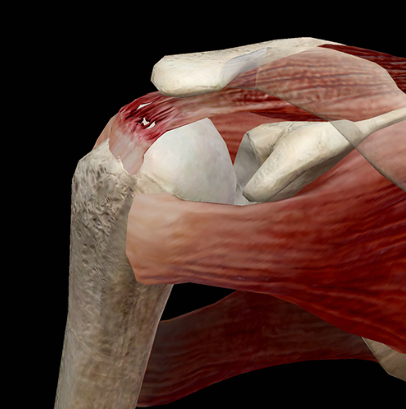

O manguito rotador é composto por quatro músculos e seus respectivos tendões:-

- Subescapular – responsável pela rotação interna do ombro.

- Supraespinhal – responsável por iniciar a abdução do braço (levantar o braço lateralmente).

- Infraespinhal – auxilia na rotação externa do ombro.

- Redondo Menor – também participa da rotação externa do ombro.